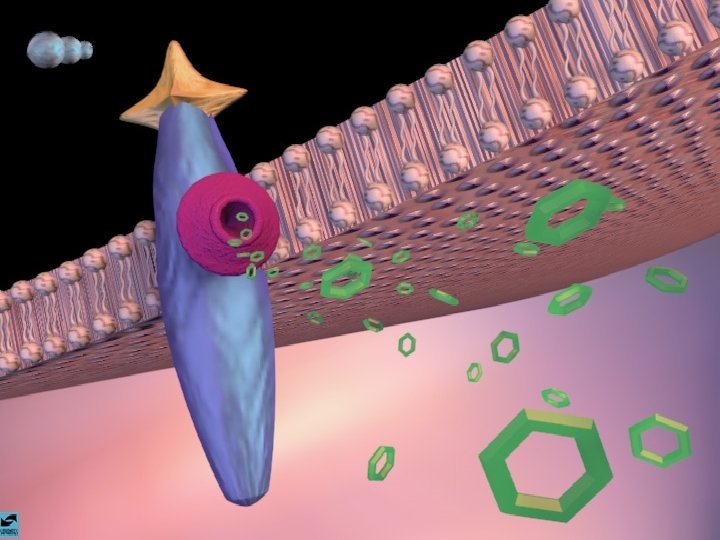

MACONHA TETRAHIDRO CANABINOL EFEITOS CEREBRAIS 1 - DISTRIBUI-SE RAPIDAMENTE POR TODO O CÉREBRO 2 - TEM AFINIDADE COM O RECEPTOR FORMADO AMANDAMIDA, QUE EXISTE NO HIPOCAMPO, TRONCO CEREBRAL E TRATO PÁLIDO 3 - AGE COMO NEUROMODULADOR ALTERANDO A PRODUÇÃO DE UM SEGUNDO MENSAGEIRO REGULADO POR OUTRO NEUROTRANSMISSOR